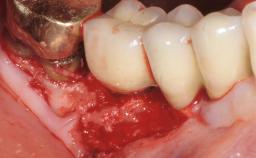

Paolo Casentini and Matteo Chiapasco present a case in which the peri-implant defect was not suitable for a fully regenerative approach. It involves implant removal, use of a CAD/CAM customized titanium mesh in the grafting phase, and placement of new implants. A 62-year-old woman was referred for consultation regarding her implant-supported prosthesis replacing teeth 14 to 16. The patient’s main concern was pain and recurrent swelling in the right posterior maxilla. The patient also reported difficulty and discomfort when brushing the area. The patient reported she had been treated in another country, where she had received three implants in combination with sinus-floor augmentation for the replacement of the posterior maxillary teeth three years earlier. The patient indicated “endodontic complications” to be the reason for the extraction of the teeth.